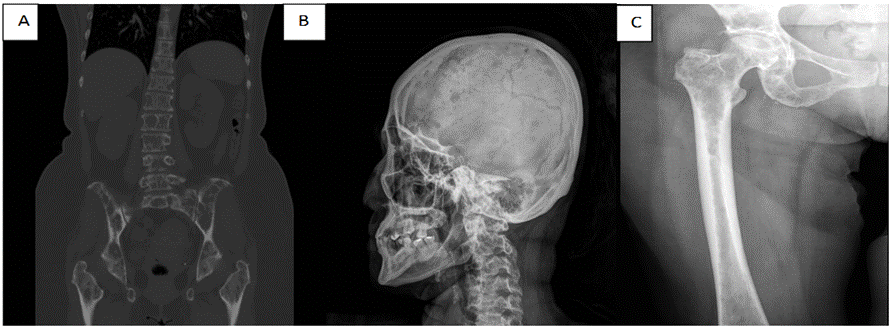

Figura 1. Lesiones osteolíticas. A. Tomografía simple (corte coronal), B. Rx simple lateral de cráneo, C. Rx simple de fémur.

Ingresa como abdomen agudo a la casa de salud, quien posterior a exámenes complementarios se observa bicitopenia, hipercalcemia, PTH no dependiente. En las imágenes fueron observadas lesiones osteolíticas en sacabocado que sugieren diagnostico presuntivo de mieloma múltiple. Se realizó una punción-aspiración de medula ósea, por el servicio de hematología. En el frotis de medula ósea fueron observadas células neoplásicas, la Biopsia de medula ósea informa carcinoma poco diferenciado de células pequeñas con inmunofenotipo CK7 positivo, receptor de estrógenos positivo, CK20 negativo.

En nuestro caso clínico la paciente acude con un síndrome constitucional acompañado de un síntoma tan inespecífico como es el dolor abdominal. A los exámenes complementarios lo que llama la atención son las radiografías de cabeza y de huesos largos con múltiples imágenes radiolúcida en sacabocados dando la impresión de proceso osteolítico. En los laboratorios al ingreso llama la atención las alteraciones en la serie roja y blanca y las plaquetas. Adicionado, a la elevación de los marcadores tumorales más empleados en el cáncer de mama. Los cuales son el CEA y el CA 15.3 (antígeno carcinoembrionario, antígeno carbohidrato 15.3). El marcador CA 15.3 es más específico a nivel ginecológico y puede elevarse de forma significativa en carcinomas de mama y ovario, aunque puede también incrementarse por otras patologías (insuficiencia renal o hepatopatías crónicas). La utilidad de dichos marcadores está en el seguimiento de las pacientes y en la valoración de la respuesta al tratamiento. Elevaciones por encima de valores normales, pueden correlacionarse con la aparición de diseminación de la enfermedad y obliga a realizar un estudio de extensión. La combinación de CEA y CA 15.3 permite diagnosticar precozmente hasta el 65 % de las recidivas tumorales de 3 a 12 meses antes de la aparición de síntomas.(9)